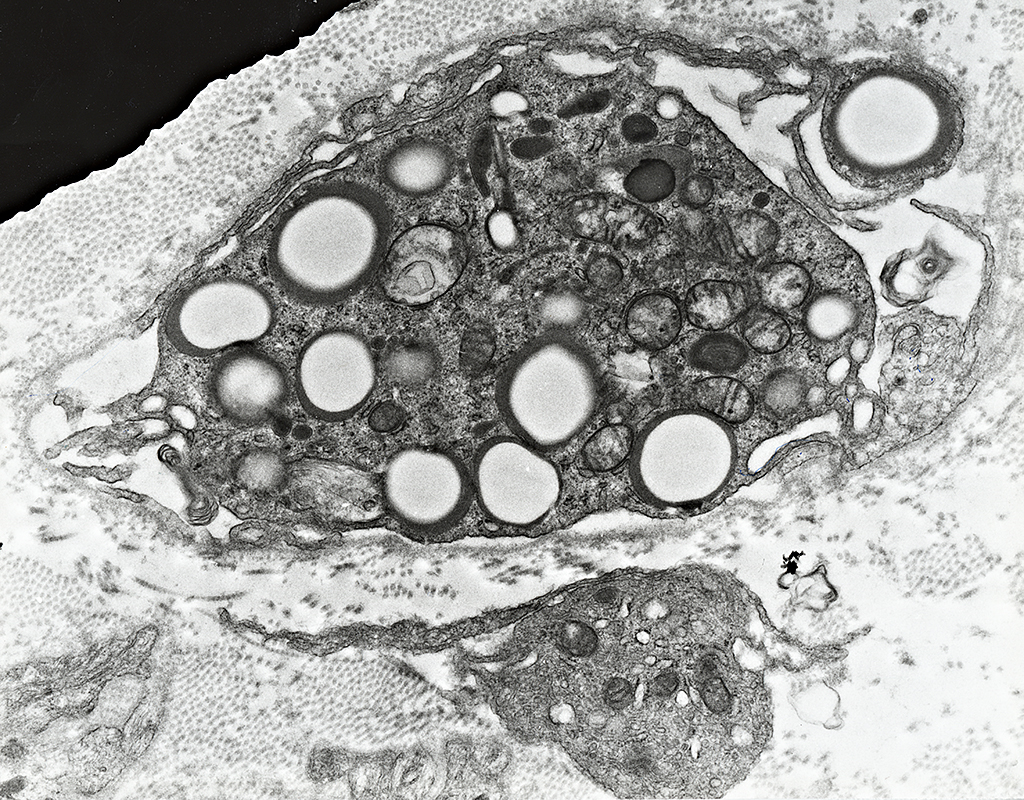

Histiocyte Ultrastructure

Histiocyte: Free in endoneurial space

Histiocyte: With lipid droplets & myelin debris

Histiocyte: Outside Schwann cell basal lamina & Myelin sheath

Histiocytes: Inside Schwann cell basal lamina

A Schwann cell process neighbors the macrophage

One large cell, with lipid debris, is inside a Schwann cell basal lamina

A second, smaller histiocyte (Below) is in the endoneurium